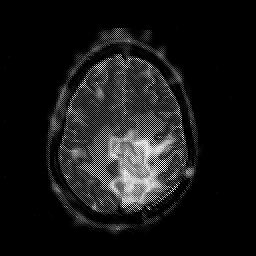

Glioblastoma multiforme overlay -- Slice #38

[Home][Help][Clinical][Tour 1][Tour 2][Tour 3] Slice 38